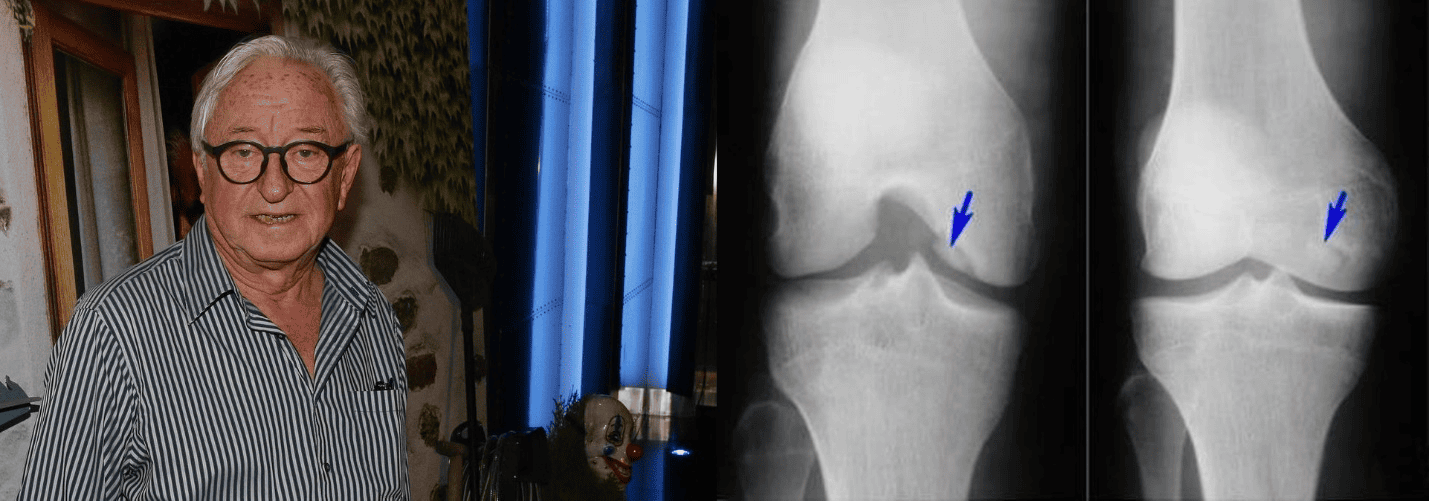

Setkali jsme se s odborníkem Jiří Lábus — MUDr. Ladislav Šenolt a povídali jsme si na téma onemocnění kloubů. MUDr. Ladislav Šenolt řekl:

MUDr. Ladislav Šenolt

MUDr., autor metodiky preventivní kineziterapie a práce s pohybovým aparátem.